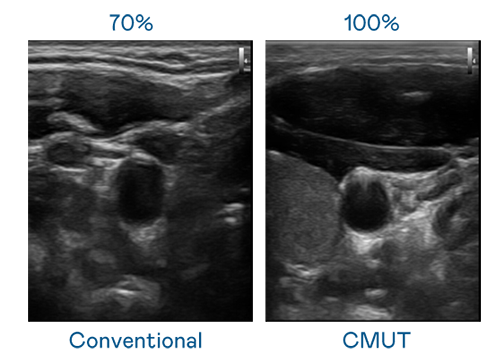

CMUT 技術是一種用電容式微機電元件來產生超音波訊號的技術。與傳統 PZT 壓電式技術相比,CMUT 頻寬增加 30%,更寬頻的超音波訊號讓影像解析度大幅提升,是實現高影像品質醫療超音波掃描、促進精準醫療發展的關鍵技術。

超音波影像的解析度高低,首先取決於探頭能發出的訊號頻寬。天游ty8 CMUT 可提供高清晰的超音波訊號,提供高頻寬、高靈敏度、影像紋理細節更高的超音波影像,協助醫護人員縮短影像判讀時間及利用精準的醫療影像進行診斷。